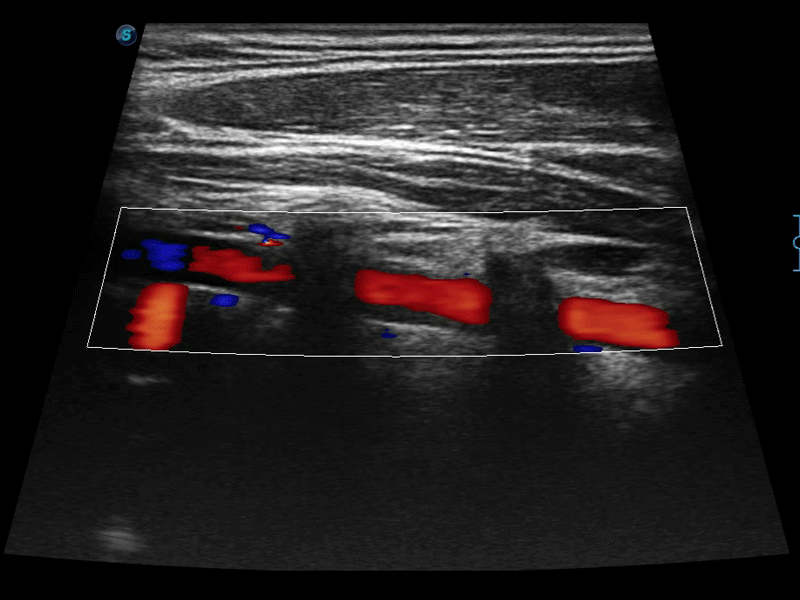

高分辨率血流成像技術(shù)提高了對低速血流信號的檢測能力。在提高空間分辨率的同時,也克服了血流外溢現(xiàn)象,為用戶提供更加真實的血流動力學(xué)信息。

通過色彩血流和實時寬景相結(jié)合,可觀察到完整的靜脈或動脈的血流,方便醫(yī)生檢查。實時掃查過程中,如有任何操作失誤也可以很容易地進(jìn)行回掃擦除,而不會中斷掃查。